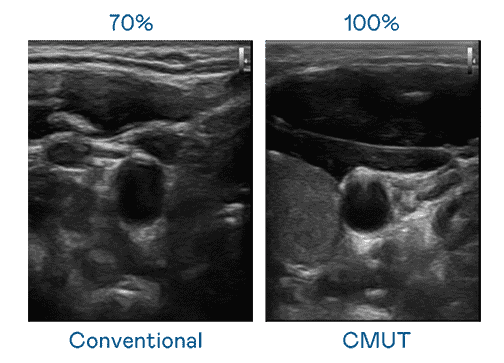

CMUT 技术是一种用电容式微机电元件来产生超音波讯号的技术。。与传统 PZT 压电式技术相比,,,CMUT 频宽增加 30%,,更宽频的超音波讯号让影像解析度大幅提升,,,,是实现高影像品质医疗超音波扫描、、、、促进精准医疗发展的关键技术。。。

大频宽带来超清晰影像

超音波影像的解析度高低,,首先取决于探头能发出的讯号频宽。。。。彩霸王 CMUT 可提供高清晰的超音波讯号,,,,提供高频宽、、、、高灵敏度、、、影像纹理细节更高的超音波影像,,,协助医护人员缩短影像判读时间及利用精准的医疗影像进行诊断。。。